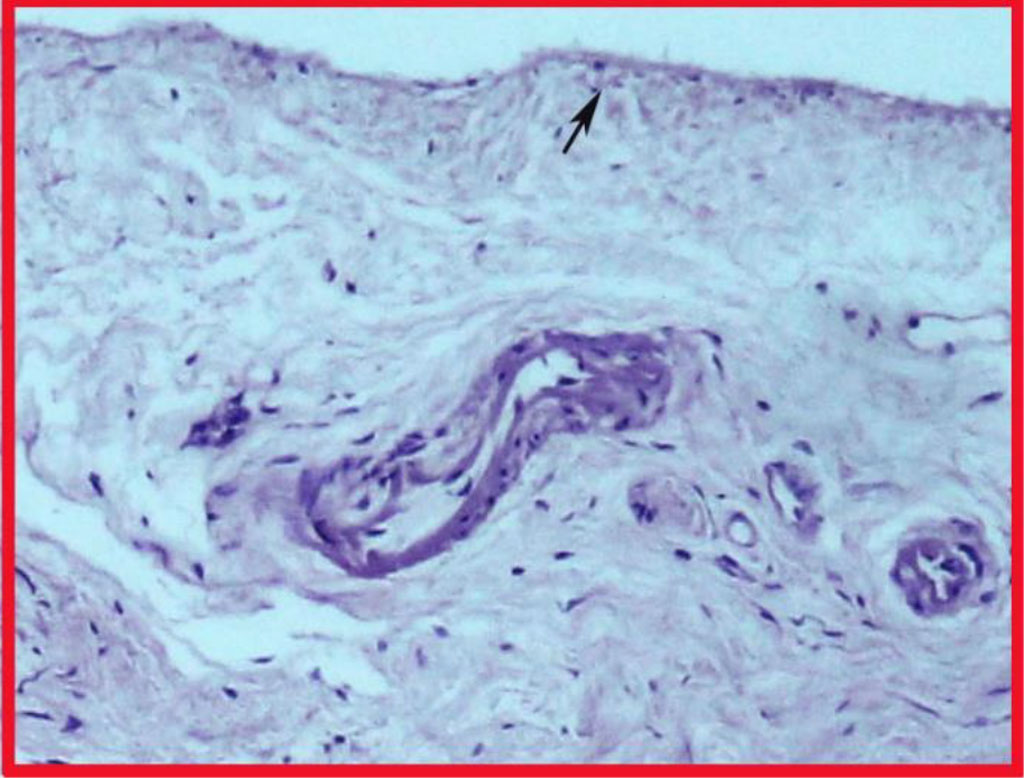

Light microscopy of the obtained Schneiderian membrane preparations showed that the general structure of the maxillary sinus mucosa is characterized by a regular layered arrangement of its constituent structures (Fig. 1). The standard was the covering multi-row ciliated epithelium localized on the basal membrane and the lamina propria of the mucosa formed by loose fibrous connective tissue. In the epithelium, there were areas of desquamation with exposure of the basal membrane. In 70% of cases, manifestations of focal or diffuse chronic productive inflammation were noted, more pronounced in the superficial layers of the mucosa. The periosteal coverage of the sinus membrane had a single-layer structure, into which fibers of the extracellular matrix from the lamina propria were woven in some areas (Fig. 1a). The fibers of the connective tissue in the periosteum layer formed a single bundle of fibers with a spatial orientation parallel to the surface of the epithelium. In all the studied objects, the inner cellular layer of the periosteum, characteristic of the classical periosteal coverage, was not visualized.

Fig. 1. Section of the Schneiderian membrane from the anterior wall of the maxillary sinus of a 49-year-old man. Staining by using hematoxylin and eosin. Magnification 100X. 1- epithelium; 2- loose connective tissue of the lamina propria; 3-periosteum.

Fig. 1a. Highlighted area in Fig. 1. Fibers interwoven into the periosteum (highlighted by the arrow).